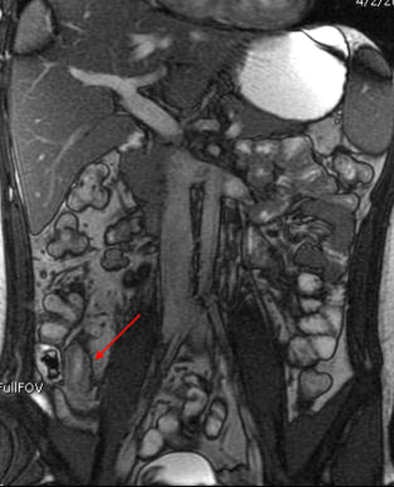

MRI results were then compared to colonoscopy and pathology reports to determine the presence or absence of disease in evaluable bowel segments. Individual imaging parameters (including wall thickening, enhancement, T2 signal, mesenteric vascular prominence, and adenopathy) were also separately analyzed to determine their independent predictive value, the authors wrote.

The study team acquired steady-state free-precession (SSFP) images of the abdomen and pelvis (TR= 4 ms, TE = 2 ms, slice thickness 8 mm for coronal images and 8-mm for axial images). Axial and coronal fat-suppressed half-fourier single-shot fast-spin echo (SSFSE) and axial spoiled-gradient images were also obtained through the abdomen, followed by T1-weighted fat-suppressed spoiled-gradient echo (LAVA/VIBE) images, before the injection of 1 mmol/kg of gadopentate dimeglumine contrast (Bayer Healthcare) followed by a saline flush and postcontrast imaging.

Mild pathologic changes are more difficult to detect with MRE or any other imaging test compared to severe changes, the authors wrote. Thus, the sensitivity of MRE for detection of pathologically mild disease was 68% in the terminal ileum and 27% in the colon, versus 87% in the ileum and 88% in the colon for severe disease. The negative predictive value of MRE was 89% for distal ileal disease and 96% for colonic disease, "indicating that MRE may successfully exclude active Crohn's disease," Grand and colleagues stated.

Interestingly, the results were in line with smaller studies that used antiperistaltic agents, they wrote. As in those studies, MRE showed its real strength in a couple of features of active Crohn's disease. "Analysis of individual MR parameters demonstrates that wall thickening and abnormal enhancement are the most sensitive indicators of Crohn's disease on MRE while abnormal T2 signal, mesenteric vascular engorgement, and adenopathy were insensitive but specific," he wrote.